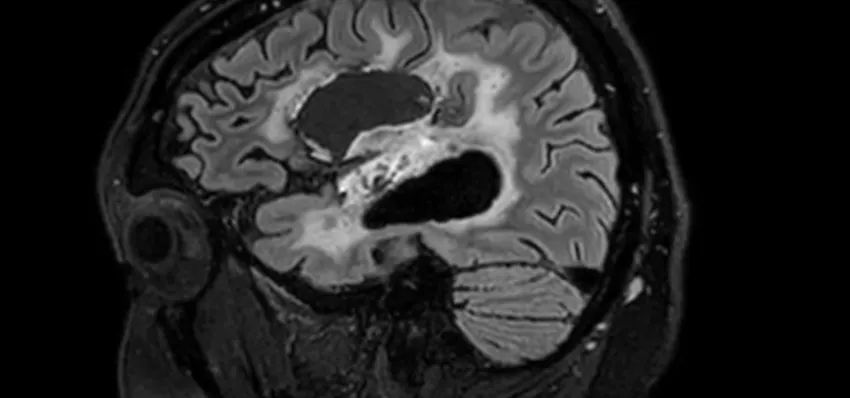

Dementia affects nearly 1 million people in the UK—stealing memories, independence, and time with loved ones. But right here in our community, Cobalt is changing that, by using advanced MRI and PET/CT scans to provide early, accurate diagnosis and also determine the effectiveness of treatment.

Dementia devastates lives—stealing memories, independence, and connections. Despite affecting nearly 1 million people in the UK, the diagnosis is often missed, and research is still underfunded. Cobalt tackles this problem with advanced brain imaging and research that leads to earlier, more accurate diagnoses and better treatments—offering families clarity, support, and hope for a different future.

Cobalt bridges the gap between diagnosis,treatment and the continued search for a cure. Using our cutting-edge MRI technology and the only PET/CT scanner in the 3 counties, we can detect dementia earlier and more accurately—especially in complex cases. Working with the NHS and researchers, we drive new clinical trials and vital discoveries. With your support, we can speed up diagnosis, unlock treatments, and train the specialists shaping the future of dementia care.